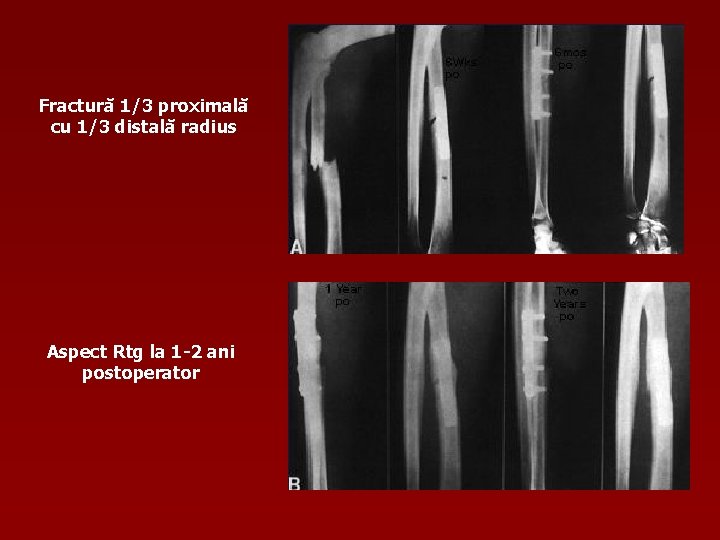

Fractură 1/3 proximală cu 1/3 distală radius Aspect Rtg la 1 -2 ani postoperator